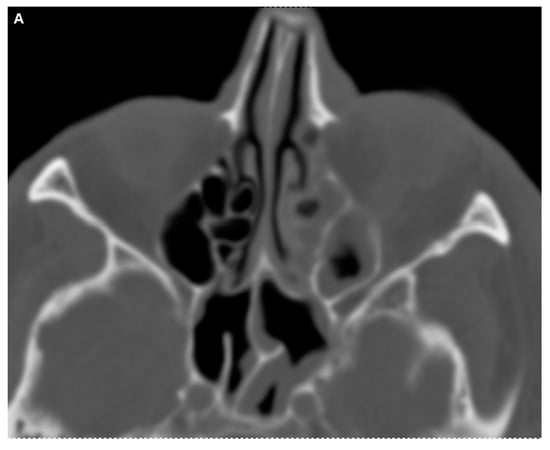

Figure 3.

CT imaging of the orbit and paranasal sinuses. The axial view reveals soft tissue swelling of the left periorbital region, with both globes appearing intact. There was no evidence of intra- or extraconal hematoma or abscess. Notably, increased vascular markings and fat imbibition within the left orbit as well as swelling of the external orbital muscles were visible, suggesting inflammatory changes. Mucosal swelling was present in the paranasal sinuses; however, the bone structures were not affected at all (A). A coronal view shows partial opacificagion of the left sphenoid sinus, which retinas some aeration. Despide this, following further consultation with ENT specialists, it was considered unlikely that the paranasal sinuses were the primary source of the patient’s symptoms. While partial opacification of the left sphenoid sinus was observed, it remained partially aerated.